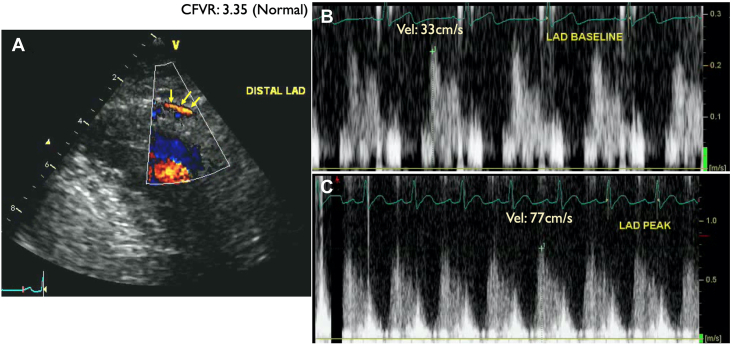

A 42-year-old man with a known family history of premature CAD and a current smoker was referred for ongoing typical chest pain for DSE after his ICA showed nonobstructive CAD (Figure 10). His DSE was terminated at the end of protocol at 85% of age-predicted maximal heart rate (at the end of 40 μg/kg/min and 1 mg atropine in addition to handgrip exercise). The rate-pressure product was 26,727 mm Hg·beats/min. At the peak test, the patient developed nonlimiting chest pain that was quick to resolve spontaneously in the recovery. The resting echocardiogram showed no RWMA, and all segments of the left ventricle augmented well during low dose. During peak stress the apical segment became thin and dyskinetic associated with the chest pain. The CFV in the distal LAD was 33 cm/s and 77 cm/s at baseline and peak, respectively, in keeping with a normal CFVR (3.35) (Figures 11 and 12, Video 4). The patient was recommended lifestyle modification and guideline-directed medical therapy. A diagnosis of coronary vasospasm was entertained.

Figure 11.

Patient 3: Coronary Flow Velocity by Doppler Echocardiography

Coronary flow velocity by Doppler echocardiography in the distal left anterior descending coronary artery (LAD) (yellow arrows indicate distal LAD color Doppler flow in diastole). LAD flow velocity reserve (CFVR) = baseline CFV/peak CFV: 77/33 = 3.35 (normal).